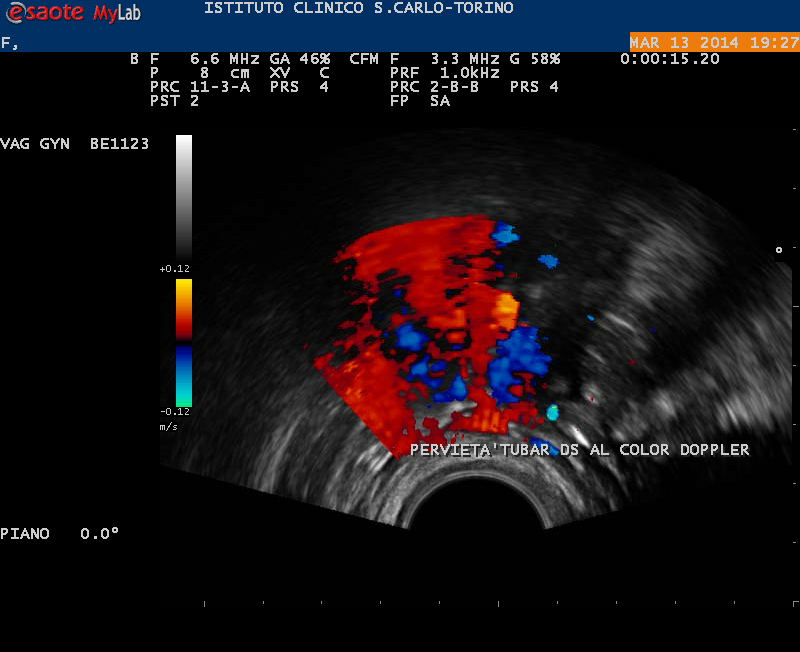

Studio della pervietà tubarica mediante sonoisterosalpingografia Una delle indagini più utili alla diagnosi di infertilità femminile da fattore tubarico riguarda lo studio della strada che gli spermatozoi devono percorrere per raggiungere l’ovocita e fecondarlo. Negli...